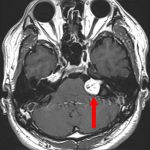

No.’25_82 手術前1

No.’25_82 手術前2